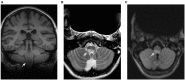

Neuromyelitis optica spectrum disorder is a rare, relapsing autoimmune disease of the central nervous system. Various initial presentations can delay diagnosis and treatment. A 14-year-old girl was admitted to the emergency department owing to respiratory insufficiency. Repeated history-taking and neuroimaging revealed an area postrema syndrome. A diagnosis of neuromyelitis optica spectrum disorder with positive aquaporin-4 antibodies has finally been established. The patient improved significantly with immunosuppressive therapy. However, her 3-year follow-up still showed sleep-disordered breathing requiring nocturnal bilevel positive airway pressure therapy. We report an original case of NMOSD leading to persistent central sleep apnea syndrome.